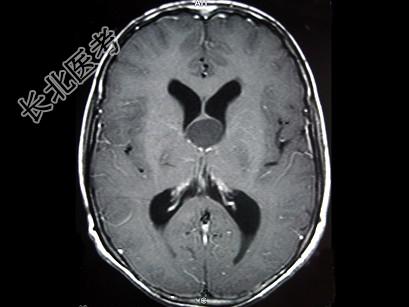

- 单项选择题女,29岁, 头痛、头昏10年,伴记忆力下降, 根据所提供图像,最可能的诊断是 ( )

A、胶样囊肿

B、蛛网膜囊肿

C、胶质瘤

D、室管膜瘤

E、表皮样囊肿